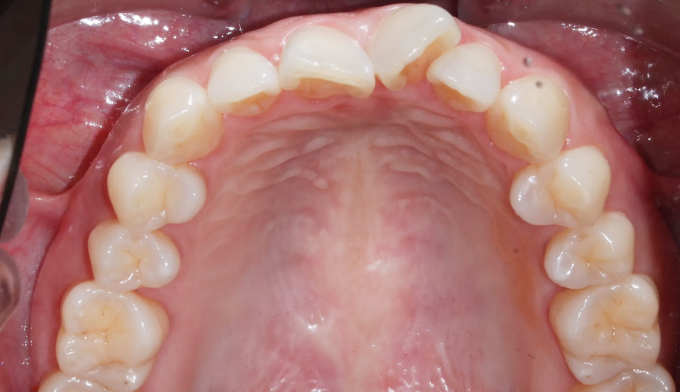

40대가 넘어가면서부터 앞니들이 점점 가운데로 몰리고 삐뚤빼뚤해지는 경우가 많습니다.

우리의 이들은 어릴적 맹출한 위치에 평생 있지 않고, 긴 시간에 걸쳐서 앞쪽으로 쏠리기 때문입니다.

삐뚤빼뚤한 정도가 심하지 않다면 간단한 앞니 부분교정만으로 충분히 배열이 가능하지만, 확보해야할 공간이 크다면 전체교정을 통해 어금니를 뒤로 보내야 앞니를 배열할 수 있는 공간을 만들 수 있습니다.

총 치료기간은 14개월 소요되었습니다.